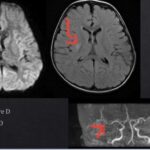

Sur l’image : les différents types d’aura visuelle possible

🔍 Aura migraineuse visuelle :

* Symptômes : Lumières scintillantes, taches aveugles (scotomes), motifs en zigzag. Ces symptômes peuvent migrer à travers le champ visuel.

🕒 Accident ischémique transitoire (AIT) :

* Symptômes : Perte soudaine de la vision centrale ou périphérique. Pas de flash lumineux, pas de zigzag.